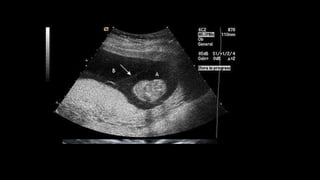

Differences in chorionicity with single placenta

D / D ( fused placenta )

• Monozygotic or dizygotic

• Thick dividing membrane

> 2mm

• Twin peak / lambda sign

M / D

• Monozygotic

• Thin dividing membrane

2mm or less

• T sign

Chorionicity should be determined at the time the twin pregnancy is detected by

ultrasound based upon the number of placental masses, the appearance of the membrane

attachment to the placenta and the membrane thickness. This scan is best performed

before 14 weeks of gestation.[New 2016] (B)